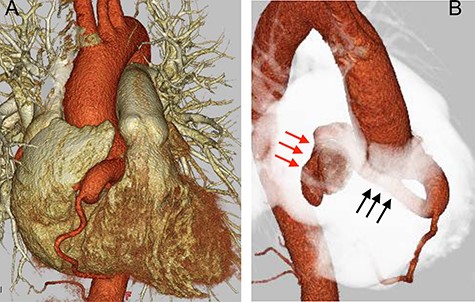

The patient was a 40-year-old woman, who had been diagnosed with a continuous heart murmur since junior high school. After being asymptomatic for many years, she became aware of angina on exertion for which she visited her family doctor. Chest X-ray revealed an enlarged heart and mild pulmonary congestion. Serology revealed a mild elevation of brain natriuretic peptide (BNP), at 77.7 pg/ml. The electrocardiogram was normal. No ischemic changes were noted on treadmill stress electrocardiogram. Transthoracic echocardiography showed normal left ventricular motion and no valvular disease. In addition, cardiac Doppler ultrasound showed continuous turbulent flow into the right atrium. Enhanced computed tomography (CT) showed a significantly dilated (13.2 mm) right coronary artery (RCA) at its origin, with a coronary artery fistulous tract draining into the posterior aspect of the right atrium. This fistula formed a large mass (21 × 29 mm) on the dorsal surface of the superior vena cava. The diameter of the RCA, distal to the fistula, was normal (Fig. 1). On right heart catheterization, intracardiac pressure data were within normal limits, but an O2 step up was observed in the right atrium, and Qp/Qs was 1.3. She was diagnosed with a right coronary aneurysm with a coronary artery fistula to the right atrium. Because of worsening of her symptoms and the presence of a large fistulous tract, the patient was considered a surgical candidate.

Preoperative CT findings; (A) frontal view; (B) upper right diagonal view; preoperation CT showed a dilated RCA (black arrow) with a diameter of 13.2 mm, and a giant aneurysm (red arrow) with an RCA-to-right atrium fistula.